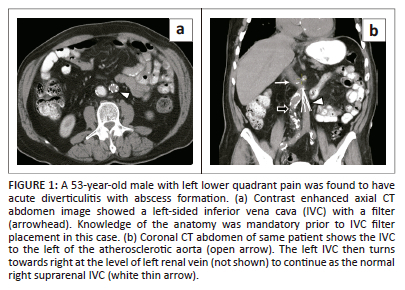

The four segments of the IVC are the hepatic, suprarenal, renal, and infrarenal segments (Table 1).4 The development of the different segments of the IVC is complex and involves the sequential appearance, anastomoses and regression of three pairs of embryonic veins, namely the posterior cardinal, subcardinal, and supracardinal veins.

During the fourth week of foetal life, the posterior cardinal veins develop and become dominant by the sixth week, responsible for the return of all the blood from the body wall caudal to the heart.5 The vitelline vein, which drains the embryonal yolk sac, is responsible for blood return from the viscera and eventually forms the hepatic segment of the IVC. The subcardinal veins become the dominant venous system by the seventh week of foetal life. The posterior cardinal veins are dorsolateral and the aorta is ventromedial to the subcardinal veins. The suprarenal segment of the IVC develops from the right subcardinal vein. By 8 weeks, the supracardinal veins predominate, positioned dorsomedial to the posterior cardinal veins and dorsolateral to the aorta. The intrathoracic course of the supracardinal veins form the azygous and hemiazygos veins. The left supracardinal vein disappears, while the right supracardinal vein forms the infrarenal segment of the IVC. The renal segment of the IVC is formed by the anastomoses between the subcardinal and supracardinal veins.1,5,6 The iliac veins derived from the persistent posterior cardinal veins form an anastomosis with the infrarenal IVC derived from the right supracardinal vein.7

Although the posterior cardinal veins do not contribute to the adult IVC, abnormality in development of the posterior cardinal veins can lead to IVC anomalies.5 Anomalies in this complex process can lead to various congenital anomalies of the IVC, which has been reported in nearly 4% of the general population (Table 2).2 Associated congenital abnormalities can occur particularly in cases with azygos continuation of the IVC, which are related to heterotaxy syndrome with left isomerism.2,8